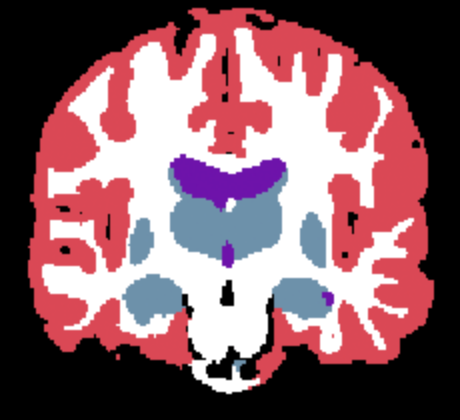

| (a) Input | (b) Ground Truth | (c) Supervised | (d) SAMSEG | (e) Naive SynthSeg | (f) Learn2Synth |

Results. Qualitative segmentation results are presented in Figure 3 and quantitative results are summarized in Table 5. Figure 3 shows that Learn2Synth produces cleaned and more accurate segmentation results compared to SAMSEG and naive SynthSeg, which is further validated by the higher Dice scores reported in Table 5. Learn2Synth also obtains higher Dice scores than the two SynthSeg variants that incorporate real data. These results highlight the effectiveness of Learn2Synth in enhancing segmentation quality for complex real-world data.